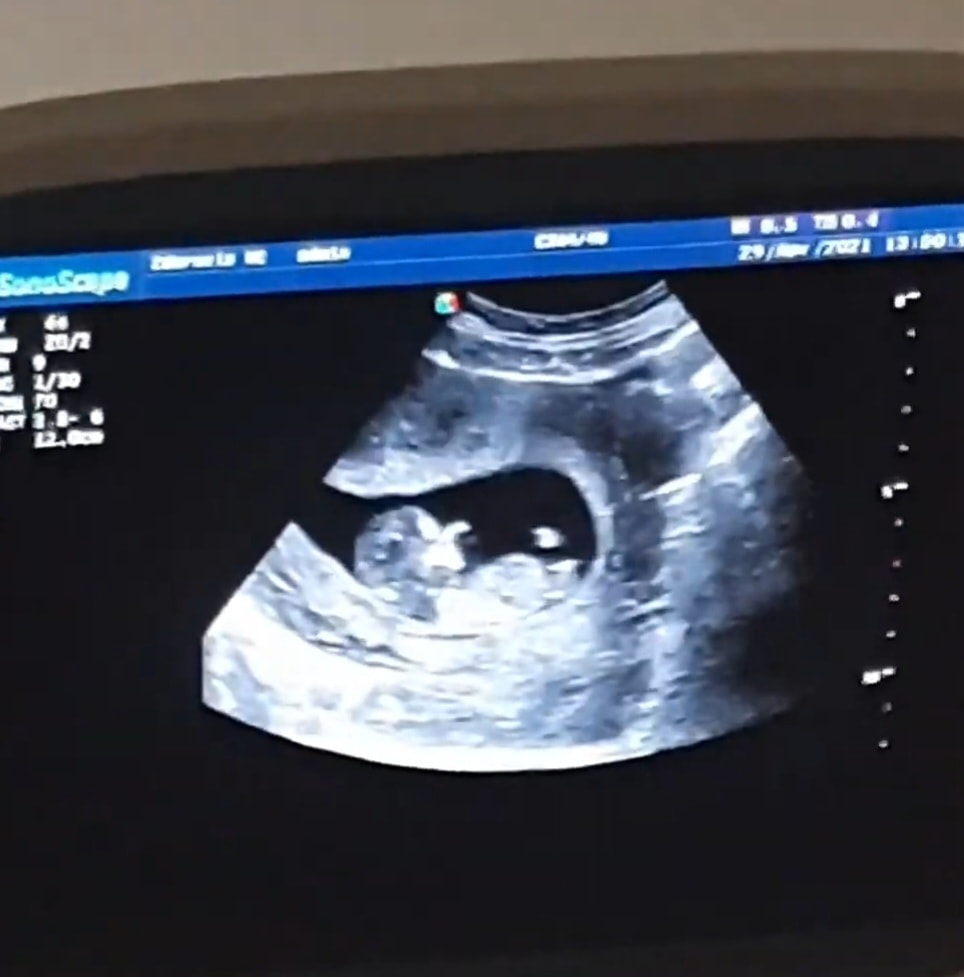

беременна, 29 неделя

Как думаете, кто будет?)))

А как вы все определяете, что девочка?))) Я вот никак не пойму кто там )))

Ольга, с линией позвоночника параллельно писюха это девочка.

Яна Кривошлыкова, ааа, спасибо ) т.е. если торчит под углом - мальчик?

Мне кажется, что сложно сказать. Вроде, по наклону девочка. Но у моего младшего сына тоже наклон был "на девочку")

И по форме головы девица.

Девочка

Девочка))

Девочка 90%